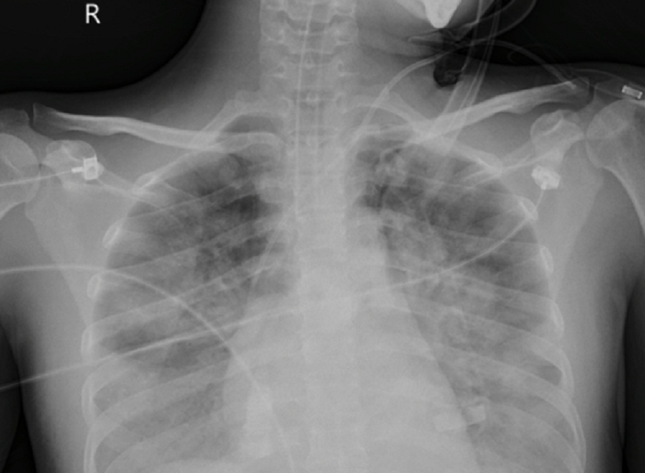

Tại đây, bệnh nhân được hồi sức chuyên sâu. Qua thăm khám, chẩn đoán hình ảnh, các bác sĩ phát hiện người bệnh bị tổn thương phổi lan tỏa hai bên chiếm gần 70% thể tích cả hai phổi. Người bệnh đã được đặt hệ thống oxy hóa qua màng ngoài cơ thể (VV-ECMO).